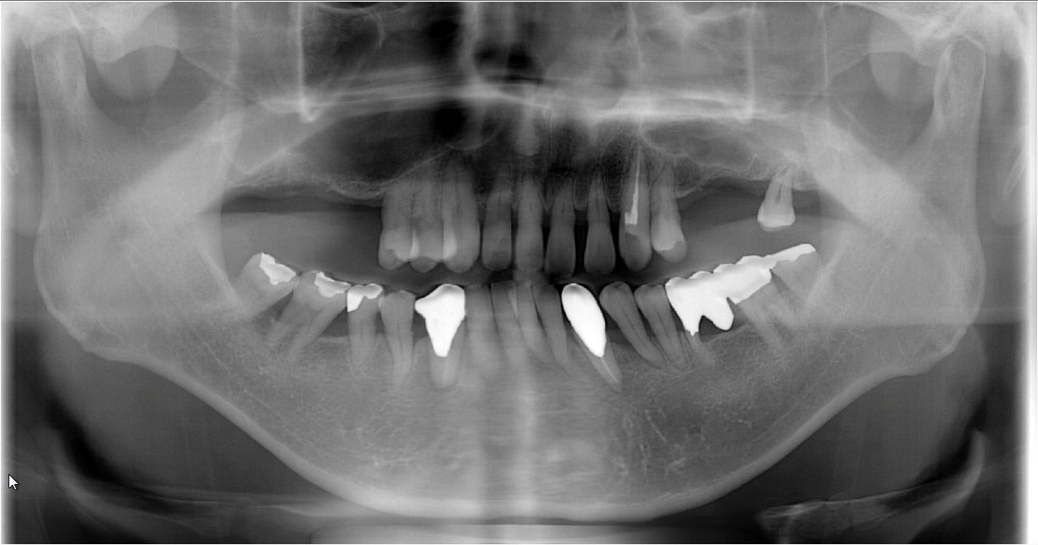

「パノラマレントゲン」は、副鼻腔や顎、上下の歯の状態を1枚の平面画像で確認できる検査です。歯の状態や周囲の組織を全体的に把握するため、治療前には必ず撮影します。

親知らずの周囲は、重要な血管や神経が複雑に絡み合っています。抜歯の際にこれらを傷つけないためには、事前に正確な情報が必要です。

当院では「CT検査」を行い、親知らず周辺の血管や神経の位置を詳細に把握します。この検査は、安全な抜歯を行うために欠かせない、大変重要なステップです。